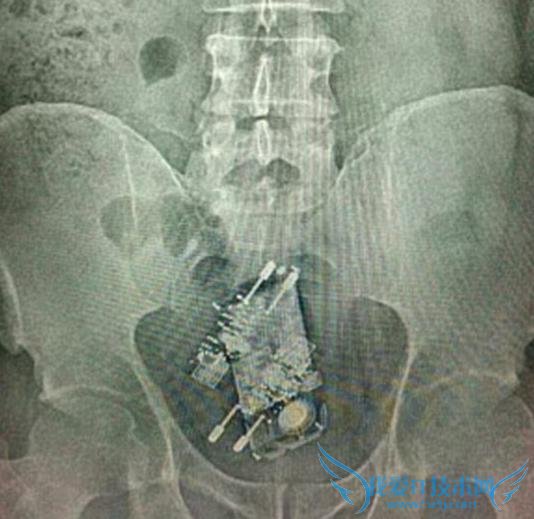

据外媒报道,近日在巴西首都巴西利亚,有一名囚犯被发现在腹中藏了一部手机和两个充电器。报道指,10 月 12 日是当地的儿童节,这在巴西是一个相当重要的节日,这名肚子藏手机的犯人在当天获得了一天的人身自由,获准离开监狱一天,但当他返回监狱时,狱警在对其进行安检时发现其腹中藏有东西。

随后,这名犯人送往当地一家医院,经过手术,医生从他体内取出了一部手机和两个充电器。经比对,取出的手机足足有纸杯般大小。监狱负责人对此表示,这名囚犯此前积攒的监狱福利都将因此而失效,他还将因为新犯下的罪受审,并接受惩罚。